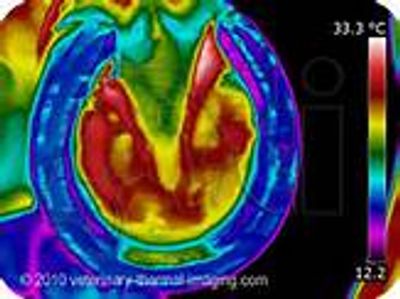

An abscess is an extremely localized infection, which is generally "walled off" within the hoof capsule. There are numerous causes for such infections; however, the primary causes are fungal infections, puncture wounds, and seedy toe. Left unattended, an abscess will migrate up the hoof capsule, following the path of least resistance, until it eventually "blows out" through the hoof wall or, often, at the coronary band , when the abscess blows out the corornary band it is called a "quittor". In this image to the left is a "solar abscess". Clearly you can see where all the red (heat) is. The abscess completely wraps around the frog area.

Thermal imaging can accurately locate an Abscess. Notice the heat in these thermal images below . Our thermal imaging cameras are very sensitive and can accurately map the temperature patterns on your horse's hoof allowing the detection of infected areas.